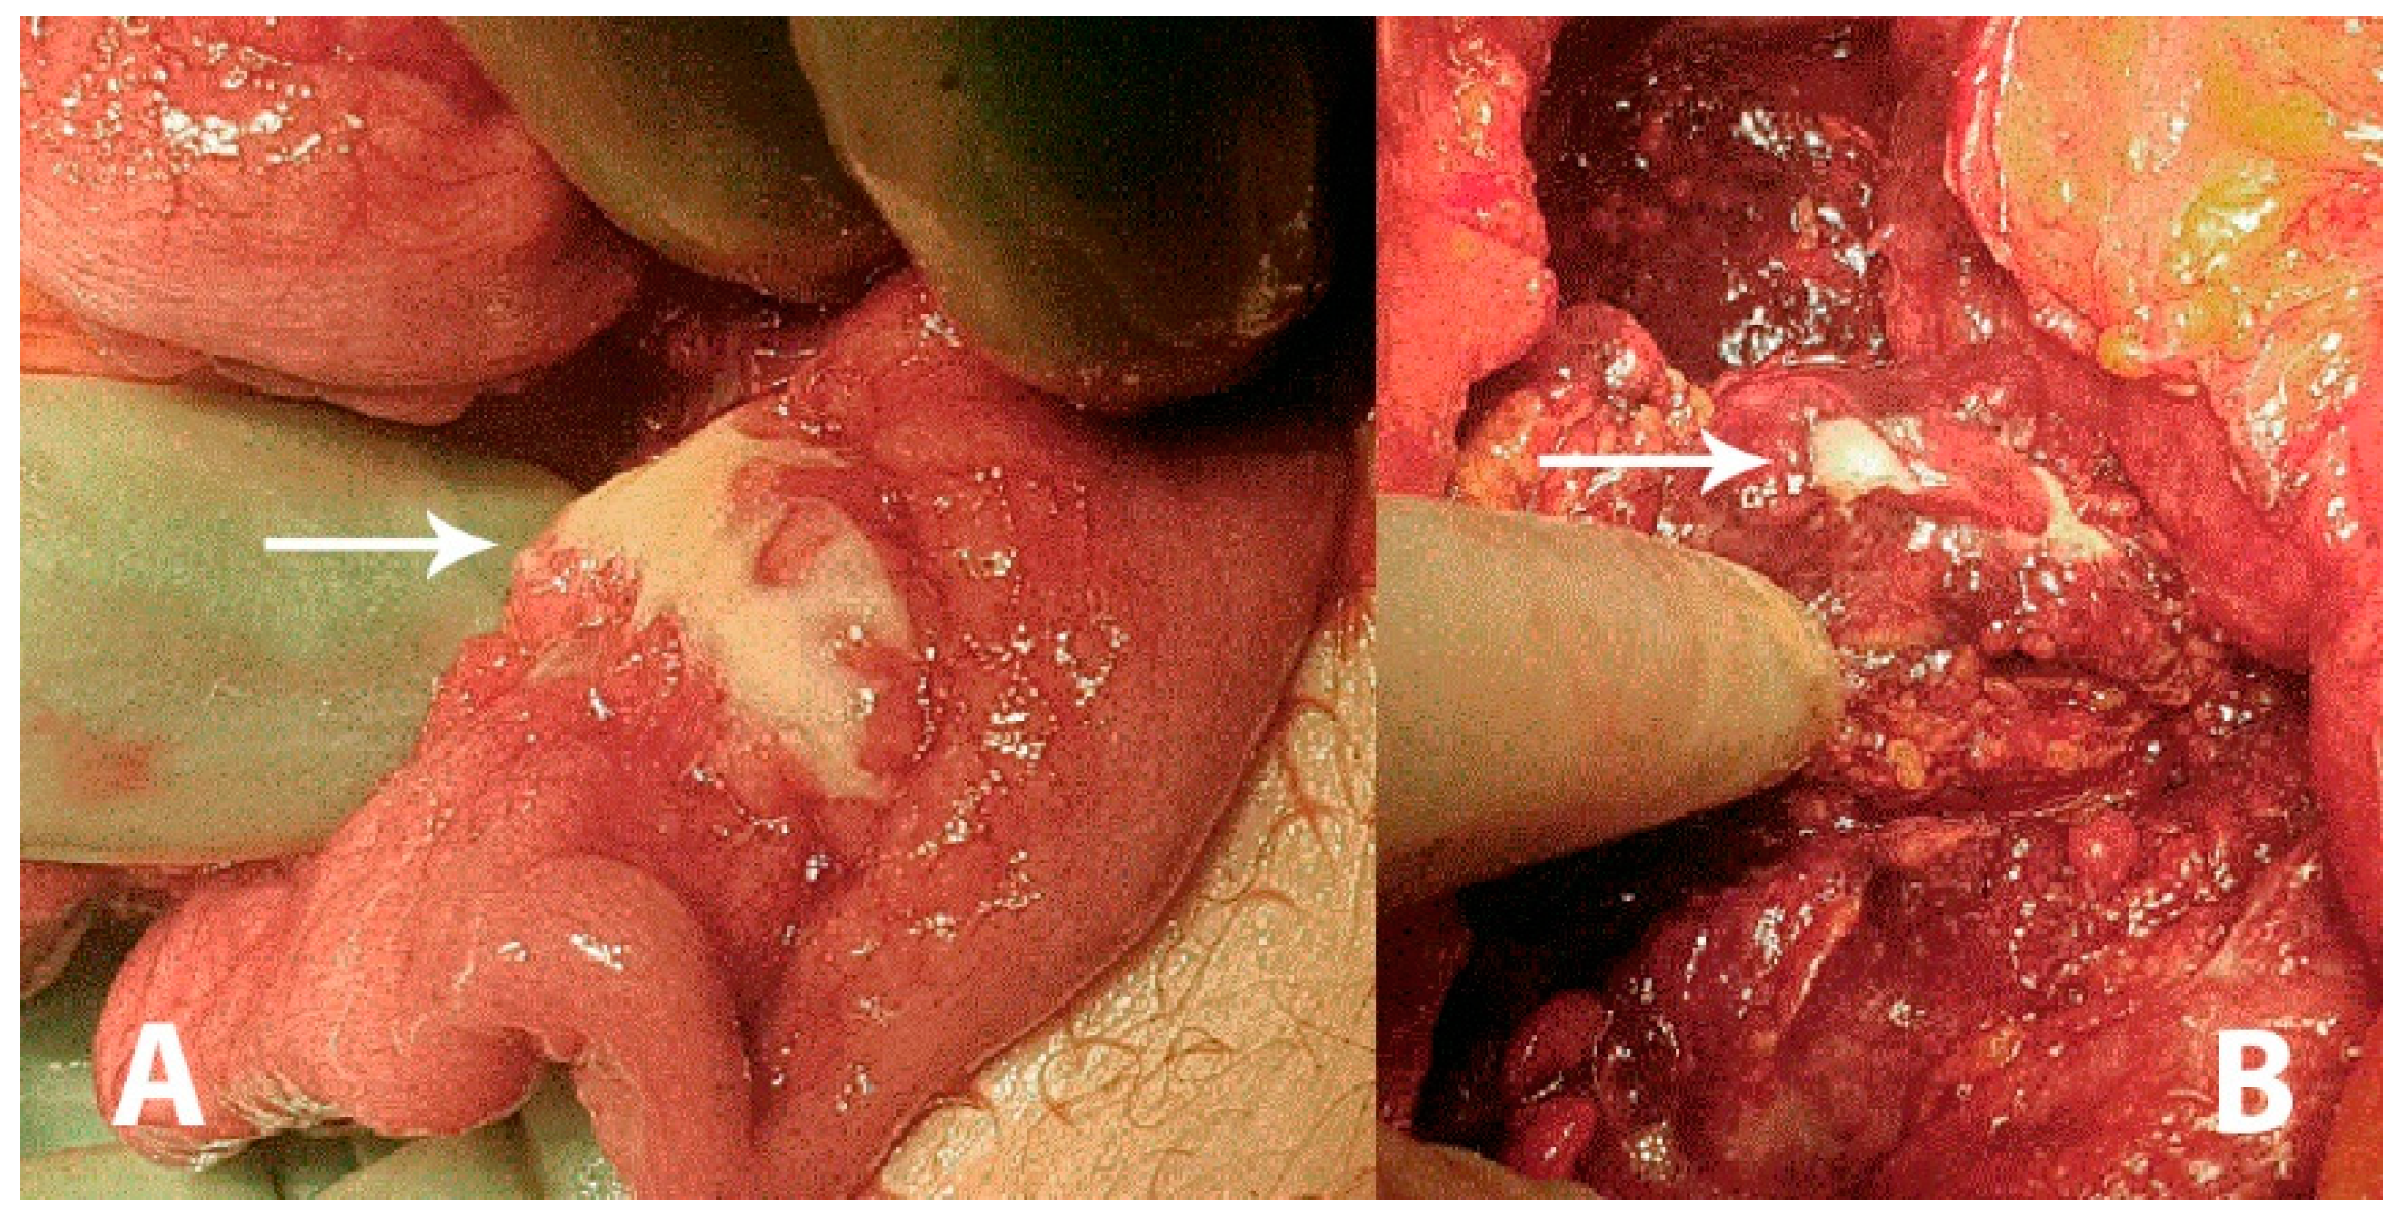

Figure 1. A 43-year-old previously healthy male was admitted to the surgical unit by his general practitioner with suspicions of acute diverticulitis. The patient complained of constant pain in the epigastric region and under the right and left rib curvature for the previous week upon admission. The pain was intensified when bending forwards and accompanied by an unspecific feeling of fatigue. The patient reported similar symptoms three weeks prior to admission, which remitted spontaneously. Any systemic symptoms of fever, unintended weight loss or night sweats were denied. At admission, the patient had a slight tachycardia; all other vital parameters were normal. Initial laboratory data came out with an elevated C-reactive protein (CRP; 176 mg/L) and a slightly elevated total leukocyte count (9.8 × 109/L). Hepatic and renal biochemical markers were within normal ranges. On physical examination the abdomen was described as tender in the upper quadrants and around the umbilicus but without peritoneal reaction. On suspicion of an intraabdominal abscess, a computed tomography (CT) scan was performed showing free liquid surrounding the liver and the spleen as well as in the small pelvis. There was no free air. However, the upper abdomen was seen with a diffuse reaction in the fatty tissue around the pylorus and ventricle. Radiologically, a perforated ulcer was suspected. The patient underwent a diagnostic laparoscopy, revealing peritonitis in all quadrants and three liters of free fluid. There were no signs of feces, pus or bile. The greater omentum was adherent in a conglomerate consisting of the duodenum, ventricle, pancreas and transverse colon. It was not possible to get a sufficient overview of the structures laparoscopically and the procedure was converted to an explorative laparotomy revealing reactive, stearin-like changes spread in the peritoneal cavity ((A,B), white arrows). The conglomerate was dissected and the posterior part of the ventricle was inspected, revealing no ulcers. The duodenum was mobilized by the Kocher maneuver, also revealing no ulcers or perforation. Perioperatively, an esophago-gastro-duodenoscopy was performed, revealing no ulcerations or pathology. A piece of the omentum was removed for histopathological examination and an intraabdominal drain was placed before ending the procedure. The findings were suspected to be caused by pancreatitis. The postoperative course was uneventful, the drain was removed after seven days and the patient was discharged after eight days with a plan of outpatient follow-up. On postoperative day 17 he was readmitted for drainage of 3.5 L ascites, which had recollected. The pancreas was without signs of pancreatitis on a triple-phase CT. Diagnostic ultrasound described no gallstones.